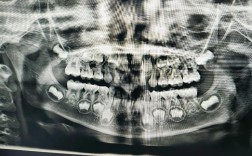

正畸像通常包括面部像(正面、侧面)、口内像(正面、左侧、右侧、上颌、下颌、咬合像),需按固定顺序拍摄,确保每次复诊条件一致。

(二)口内像:清晰记录牙齿与咬合

口内拍摄需借助口撑拉开颊部,配合环形闪光灯减少阴影,操作时动作轻柔,避免患者恶心。

| 像别 | 拍摄角度 | 关键要点 |

|---|---|---|

| 口内正面像 | 镜头与咬合平面平行,患者张口自然 | 对焦中切牙,暴露全口牙齿,避免舌体遮挡;光圈f/11-f/16,确保前后牙清晰。 |

| 口内左侧像 | 患者头部稍向右转,镜头对准左侧 | 拍摄左侧牙齿排列、颊侧黏膜,对焦第一磨牙,捕捉咬合关系。 |

| 口内右侧像 | 患者头部稍向左转,镜头对准右侧 | 同左侧像,注意对称性,避免光线不均。 |

| 上颌像 | 患者头部后仰,镜头从上方拍摄 | 拉开上唇,暴露上颌牙齿,注意腭部形态,避免咽部阴影。 |

| 下颌像 | 患者头部前倾,镜头从下方拍摄 | 拉开下唇,暴露下颌牙齿,捕捉舌侧形态,避免舌体遮挡。 |

| 咬合像 | 患者牙齿咬于正中颌位,镜头与咬合平面平行 | 对准咬合面,记录上下牙接触关系,光圈适当缩小(f/16),确保上下牙列清晰。 |